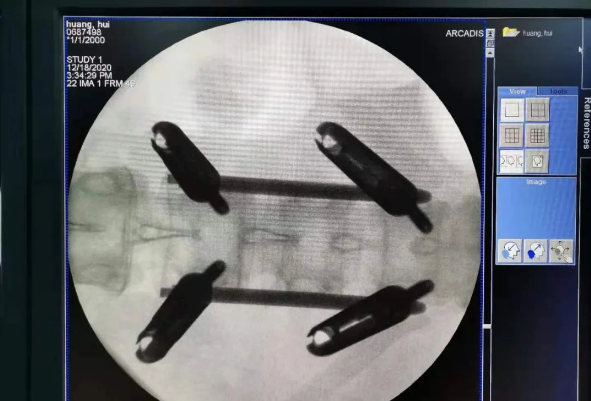

克日,天玑?骨科手术机械人落户南昌市第一医院,助力骨盆骨折闭合复位内牢靠术顺遂完成。作为江西省首先接纳5G指导下的骨科机械人手术,天玑?骨科手术机械人用它的“透视眼”,以三维影像扫描举行深层三维空间精准定位,为患者“量身定做”了最理想、最清静的教科书般通道,完成了重大骨盆骨折微创治疗一次性完善置钉及腰椎骨折微创经皮置钉的首秀,成为江西省骨科生长的标记性事务,同时也是江西省骨科步入新型数字智慧骨科时代的主要里程碑事务。

我国自主研发的天玑?骨科手术机械人,是针对骨骼硬组织的先进手艺,已经获得国际认可,能够开展脊柱全节段 (颈椎、胸椎、腰椎、骶椎) 疾病、骨盆和四肢等骨折、骨肿瘤以及枢纽导航等手术。相比古板手术,机械人辅助手术具有手术创伤小、出血少、并发症少、康复快的优势。同时,由于不需通过重复透视来确定置钉位置,从而能镌汰术中辐射,大大降低患者辐射危害,且手术历程中,由机械人与主刀医师配合完成手术,大大增添了手术清静性。

在南昌市第一医院廖琦教授向导下,由创伤骨科团队借助天玑?骨科手术机械人为患者“量身定做”最理想、最清静的教科书般的通道,完善清静微创完成手术,并且手术时间显着缩短,真正做到“指哪儿打哪儿”!更让患者定心的是,天玑?骨科手术机械人的“稳固手”机械臂举行精准定位,不必重复探寻。

由于天玑?骨科手术机械人的精准及高效,可以使手术时间显着缩短,因此在骨盆骨折手术后,在廖琦教授指导下,脊柱外科团队使用天玑?骨科手术机械人同样为20岁女性腰椎骨折患者“量身定做”最理想、最清静的教科书般的通道,完善清静微创完成手术,手术不但时间缩短,并且出血和透视镌汰。